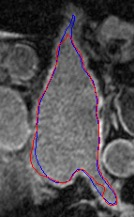

Automated segmentation in medical image analysis is a challenging task that requires a large amount of manually labeled data. However, most existing learning-based approaches usually suffer from limited manually annotated medical data, which poses a major practical problem for accurate and robust medical image segmentation. In addition, most existing semi-supervised approaches are usually not robust compared with the supervised counterparts, and also lack explicit modeling of geometric structure and semantic information, both of which limit the segmentation accuracy. In this work, we present SimCVD, a simple contrastive distillation framework that significantly advances state-of-the-art voxel-wise representation learning. We first describe an unsupervised training strategy, which takes two views of an input volume and predicts their signed distance maps of object boundaries in a contrastive objective, with only two independent dropout as mask. This simple approach works surprisingly well, performing on the same level as previous fully supervised methods with much less labeled data. We hypothesize that dropout can be viewed as a minimal form of data augmentation and makes the network robust to representation collapse. Then, we propose to perform structural distillation by distilling pair-wise similarities. We evaluate SimCVD on two popular datasets: the Left Atrial Segmentation Challenge (LA) and the NIH pancreas CT dataset. The results on the LA dataset demonstrate that, in two types of labeled ratios (i.e., 20% and 10%), SimCVD achieves an average Dice score of 90.85% and 89.03% respectively, a 0.91% and 2.22% improvement compared to previous best results. Our method can be trained in an end-to-end fashion, showing the promise of utilizing SimCVD as a general framework for downstream tasks, such as medical image synthesis and registration.